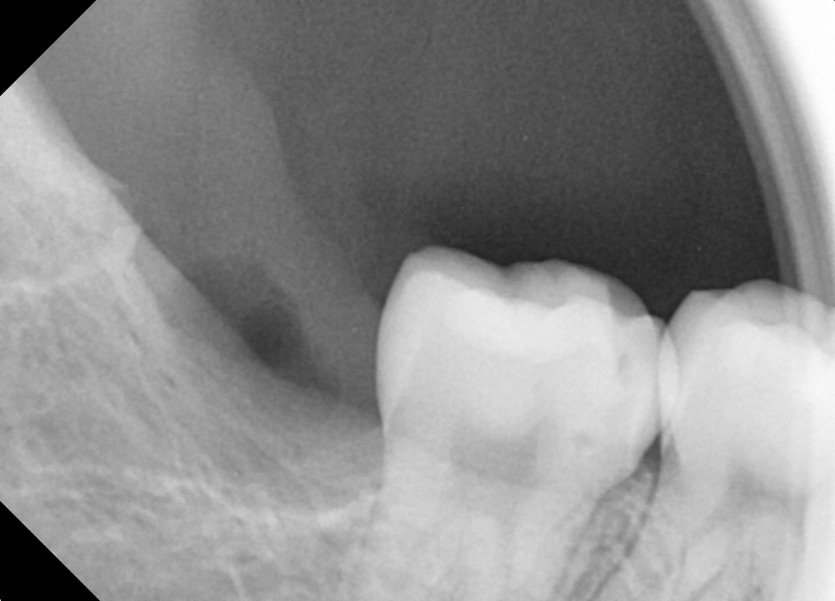

#18,28,38,48 사랑니 발치

구강 외과 전문의가 당일 발치했습니다.